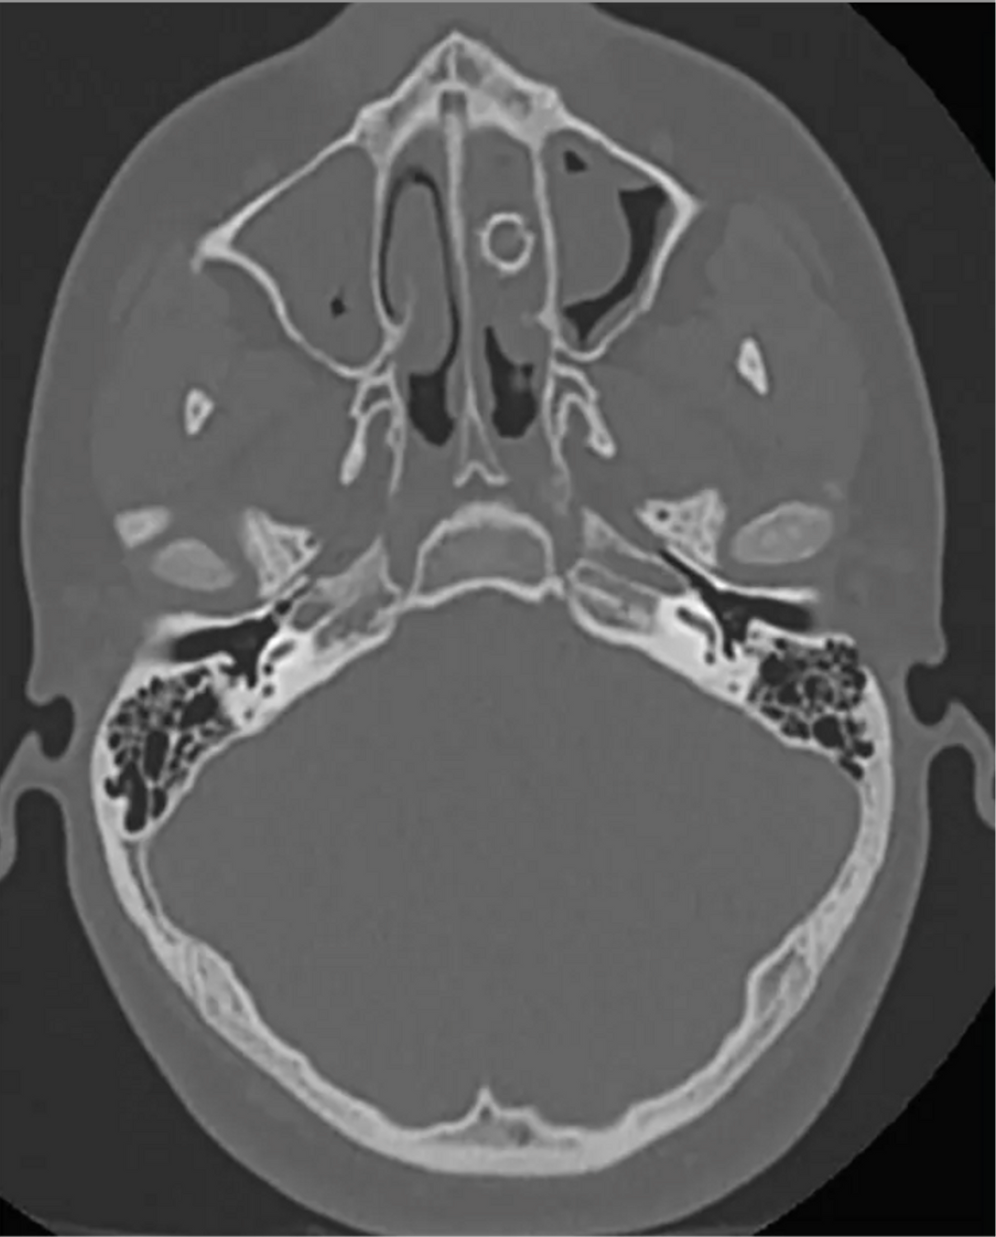

"Der Patient berichtete, dass er nicht das Gefühl hatte, schlechten Atem zu haben, aber es war ihm peinlich, dass jedes Mal, wenn er sich die Nase putzte, dieser Geruch entstand", so die Studienautoren. Der 16-Jährige wurde erneut untersucht. Mithilfe eines CT-Scans entdeckten die Mediziner schließlich eine neun Millimeter große kugelförmige Struktur in der Nasenhöhle des Jugendlichen.

Die Ärzte entfernten den Fremdkörper in einer anschliessenden Operation: Das mysteriöse Objekt, das von Gewebe überwachsen war, entpuppte sich als Metallkugelgeschoss, wie es in Luftgewehren verwendet wird. Doch wie war das dorthin gekommen?